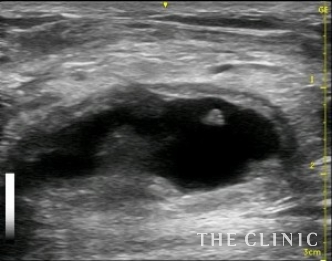

今回は5cm以上の充実性で、被膜が厚いしこりのため乳輪切開の摘出をすすめましたが、傷を作りたくないという希望があり、ベイザーリポによる治療を選択しました。術前のエコー像です。ベイザーで壊死脂肪を崩して吸引します。

ほとんど内容物は消失しました。2か月後にしこりの部位が硬くなったため来院するとしこりの被膜内にリンパ液が貯留していました。

これをエコー下に穿刺吸引しました。

ベイザーリポによる充実性のしこり治療は被膜が残存するので5㎝以上のしこりの場合はこのようにリンパ液が貯留することがありますが、何度かエコー下に穿刺吸引することで貯留しなくなります。